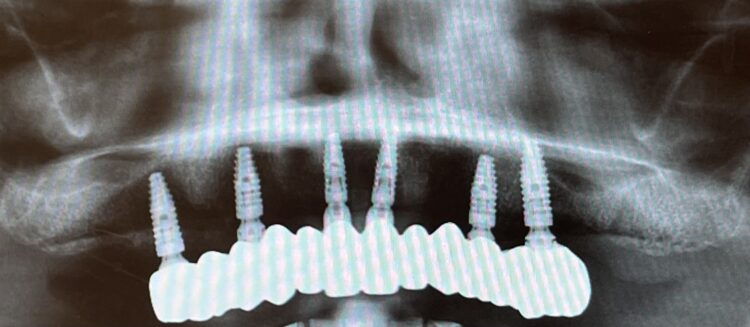

The implant beds were then prepared with the surgical guide in situ. Six CONELOG® Progressive-Line implants from BioHorizons Camlog were placed in accordance with the predetermined positions, depths and angulations. These implants were selected for this case because they feature an optimal thread design and tapered figure, promoting high primary stability – which is essential in full arch reconstruction cases.

The implants were placed through the guide for better accuracy and precision. A surgical primary stability of >35Ncm was achieved for each implant. Once the implants were placed, the surgical guide was removed, and the extraction of the remaining teeth was completed.

This phase of treatment concluded with radiographs to confirm accurate implant placement. The patient was also given standard post-operative oral hygiene and care instructions. He reported no complications or concerns during the review appointment a week later.

Based on the digital design and copying the approved provisional prosthesis, a zirconia overlay was milled. The overlaying zirconia superstructure was digitally designed to fit the metal substructure, accomplish a flawless finish line, avoid any undercuts and verify the path of insertion, thus facilitating the bonding procedures. The zirconia superstructure was bonded with the titanium substructure using a self-curing luting composite. The final polished screw-retained prosthesis was delivered and torqued to 30Ncm and the radiographic assessment was executed.